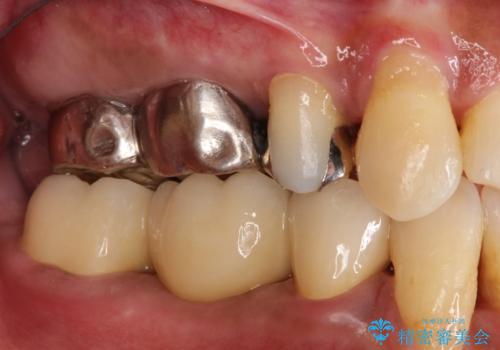

- 奥歯が痛いことを主訴に来院されました。

遠心根に歯根破折を認め、保存不可と判断しブリッジにて欠損補綴を行なっております。

歯根の縦方向への破折は保存不可となることが多いです。

今回は抜歯後、オールセラミックにて修復を行うことで審美性の高い治療を行うことができました。